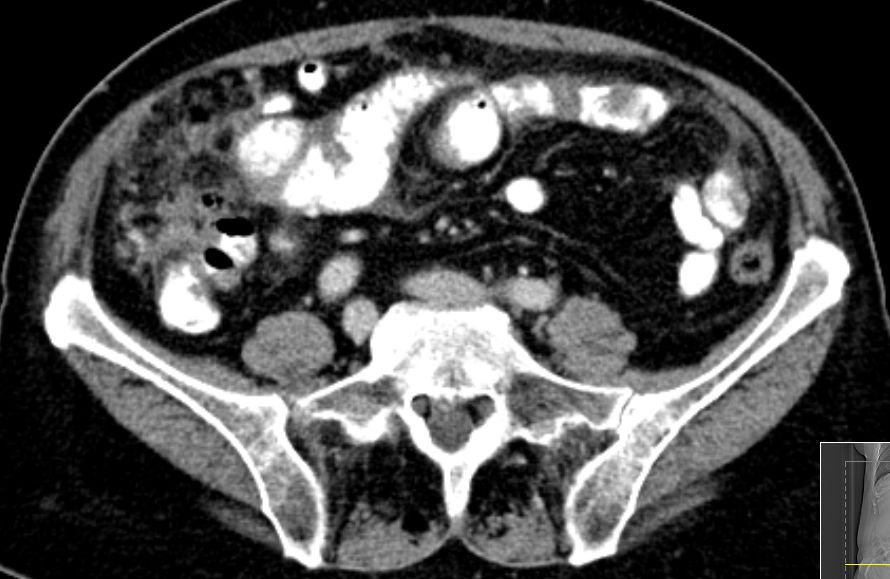

72-jährige Frau mit Peritonealkarziose nach HE mit

Adnexen vor 16 Jahren.

Histologie: Low-grade-serös-papilläres Karzinom

Intraoperatv ausgedehnte Karzinose der Darmserosa und des

Mesenteriums.